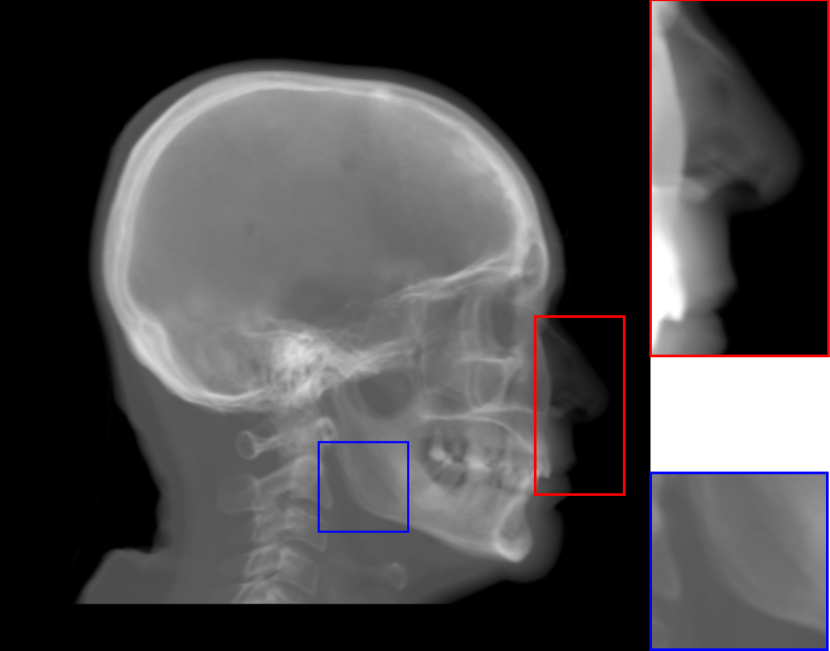

Refer to caption

(a) Real cephalogram

(b) Synthetic cephalogram

(c) Plot of samples and sigmoid curves

Fig. 2: Image contrast difference between real conventional cephalograms and RayCast synthetic cephalograms: (a) a real cephalogram example; (b) a RayCast synthetic cephalogram example; (c) the plot of samples between RayCast synthetic cephalograms and real cephalograms with an original sigmoid curve (red) and our proposed modified sigmoid curve (blue).

In Fig. 2, one real conventional cephalogram example and one example of 𝒈𝒈\boldsymbol{g} are displayed, where evident image contrast difference between these two images is observed. It is because the X-ray films used in conventional cephalograms have the special nonlinear optical property that the characteristic curve between optical density and logarithmized X-ray exposure has a sigmoid-like shape [42]. According to the Lambert-Beer law, the logarithmized X-ray exposure is equivalent to the attenuation integral. It indicates that the intensity relation between the desired cephalogram and the attenuation integral image 𝒈𝒈\boldsymbol{g} should also exhibit a sigmoid-like curve. Therefore, to make the image contrast of synthetic cephalograms similar to conventional cephalograms, a sigmoid intensity transform is necessary.

To find the parameters for the above general sigmoid transform, the mean intensity values of samples chosen in certain regions of 𝒈𝒈\boldsymbol{g} together with the corresponding values sampled from real conventional cephalograms are plotted as black dots in Fig. 2(c). The sigmoid transform of Eqn. (4) is plotted as the red-dotted curve, whose parameters are determined by least squares curve fitting. As displayed, most samples are located near the sigmoid curve, which is consistent with the characteristic curve in X-ray films. Note that the positions of the samples are approximated very coarsely due to the absence of dental CBCT volumes and their corresponding cephalograms. With matching pairs, a more accurate intensity transform can be learned.

where the intensity transform is a modified sigmoid function, illustrated as the blue-dotted curve in Fig. 2.

The synthetic cephalograms generated by different methods are displayed in Fig. 8. Figs. 8(a) and (b) show the cephalograms synthesized by the orthogonal [33] and perspective [21] RayCast methods, respectively, which are the most widely used methods for cephalogram synthesis from CBCT volumes. Comparing Fig. 8(b) to Fig. 8(a), due to different magnification factors of structures at different positions in perspective projection, anatomical structures on both sides of the midsaggital plane cannot overlap well, for example, the projections of the left and right mandible (gonial) angles in the zoom-in ROI in Fig. 8(b). In Figs. 8(a) and (b), the skeleton structures, soft tissues and airways are well observed. However, the image contrast in these two synthetic cephalograms are different from conventional cephalograms (Fig. 2(a)). The cephalogram synthesized by MIP using the largest 100 pixels along each orthogonal ray is displayed in Fig. 8(c). In this subfigure, skeleton structures are well observed since they have high intensity. Nevertheless, low intensity structures, e.g. the throat airway, might disappear. The CycleGAN [59] synthetic cephalogram is shown in Fig. 8(d). Compared with the conventional cephalogram example in Fig. 2(a), it has the closest image contrast. Hence, it achieves the best perceptual index of 5.53. However, some detailed anatomical structures are incorrect. For example, the nose has extremely low intensity in the zoom-in ROI. It also suffers from geometric distortion. As a consequence, the stitching artifacts are visible.

Figure 8(e)-(g) are the Type I synthetic cephalograms of different steps using orthogonal projection. Fig. 8(e) is the orthogonal RayCast celphalogram synthesized from the enhanced CBCT volume using Eqn. (1). Compared with Fig. 8(a), skeleton structures in Fig. 8(e) have higher contrast. Fig. 8(f) is obtained by applying the original sigmoid transform in Eqn. (4) to Fig. 8(e), where the skeleton structures are further enhanced. Moreover, the appearance of Fig. 8(f) is very close to conventional cephalograms. However, the soft tissues like the nose and lips have an almost constant intensity value, as displayed in the zoom-in ROI in Fig 8(f). The final Type I synthetic cephalogram with orthogonal projection is displayed in Fig. 8(g). With the proposed modified sigmoid transform in Eqn. (6), the contrast in the soft tissues is brought back, as displayed in the zoom-in ROI. For comparison, the final Type I synthetic cephalogram with perspective projection is displayed in Fig. 8(h). Compared with Fig. 8(g), the mandible angles in the zoom-in ROI of Fig. 8(h) are not overlapped well due to perspective magnification.